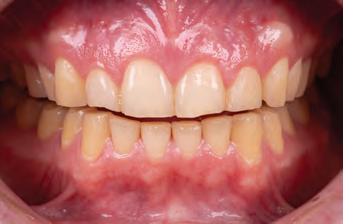

A 31-year-old woman presented with cosmetic concerns regarding her smile and requested a conservative enhancement. After clinical and radiographic analysis, digital 35mm photographs were taken and reviewed by the restorative clinician, technician, and surgeon (Fig 1). A digital impression was taken of the maxillary and mandibular arches using an intraoral scanner (Trios 3, 3Shape; Fig 2), and a smile design was developed with NemoSmile Design 3D software (Nemotec; Fig 3a). This allows for a facially driven smile frame to be created using reference lines of facial and smile proportions and natural teeth shapes and textures from the digital library (Fig 3b).

After developing the simulated mock-up, a 3D-printed resin model was created using CAD software (Fig 4a), and a clear PVS matrix (Exaclear, GC America) was fabricated to replicate the printed diagnostic wax-up using a nonperforated tray (Fig

Fig 1 Preoperative clinical views of a 31-year-old woman presenting with diastemas and limited tooth visibility. (top) Portrait. (center row) Intraoral views. (bottom row) Smile.

4b). This matrix was used to create an intraoral motivational mock-up with bis-acryl composite (Luxatemp Ultra, DMG). This additive mock-up provides the interdisciplinary team with an intraoral translation for evaluation (Fig 5). Upon evaluation of the digital smile frame and the clinical translation, it was determined that multiple esthetic and restorative requirements were necessary for an optimal biologic framework, and the interdisciplinary team determined the best sequence for these procedures. The patient was presented with the interdisciplinary treatment possibilities that included restoring the maxillary anterior teeth and premolars with a minimally

invasive preparationless procedure or with less conservative veneer preparations. The restorative materials discussed included injectable resin composites and ceramic (ie, feldspathic, pressable, machinable). For an optimal biologic framework and health, it was determined that connective tissue grafting would be necessary for treatment of the recessiontype defects on the maxillary left central and lateral incisors, canine, and premolars. The patient opted for the conservative preparationless composite veneers using the injectable resin technique followed by a connective tissue surgical procedure using the tunneling technique.